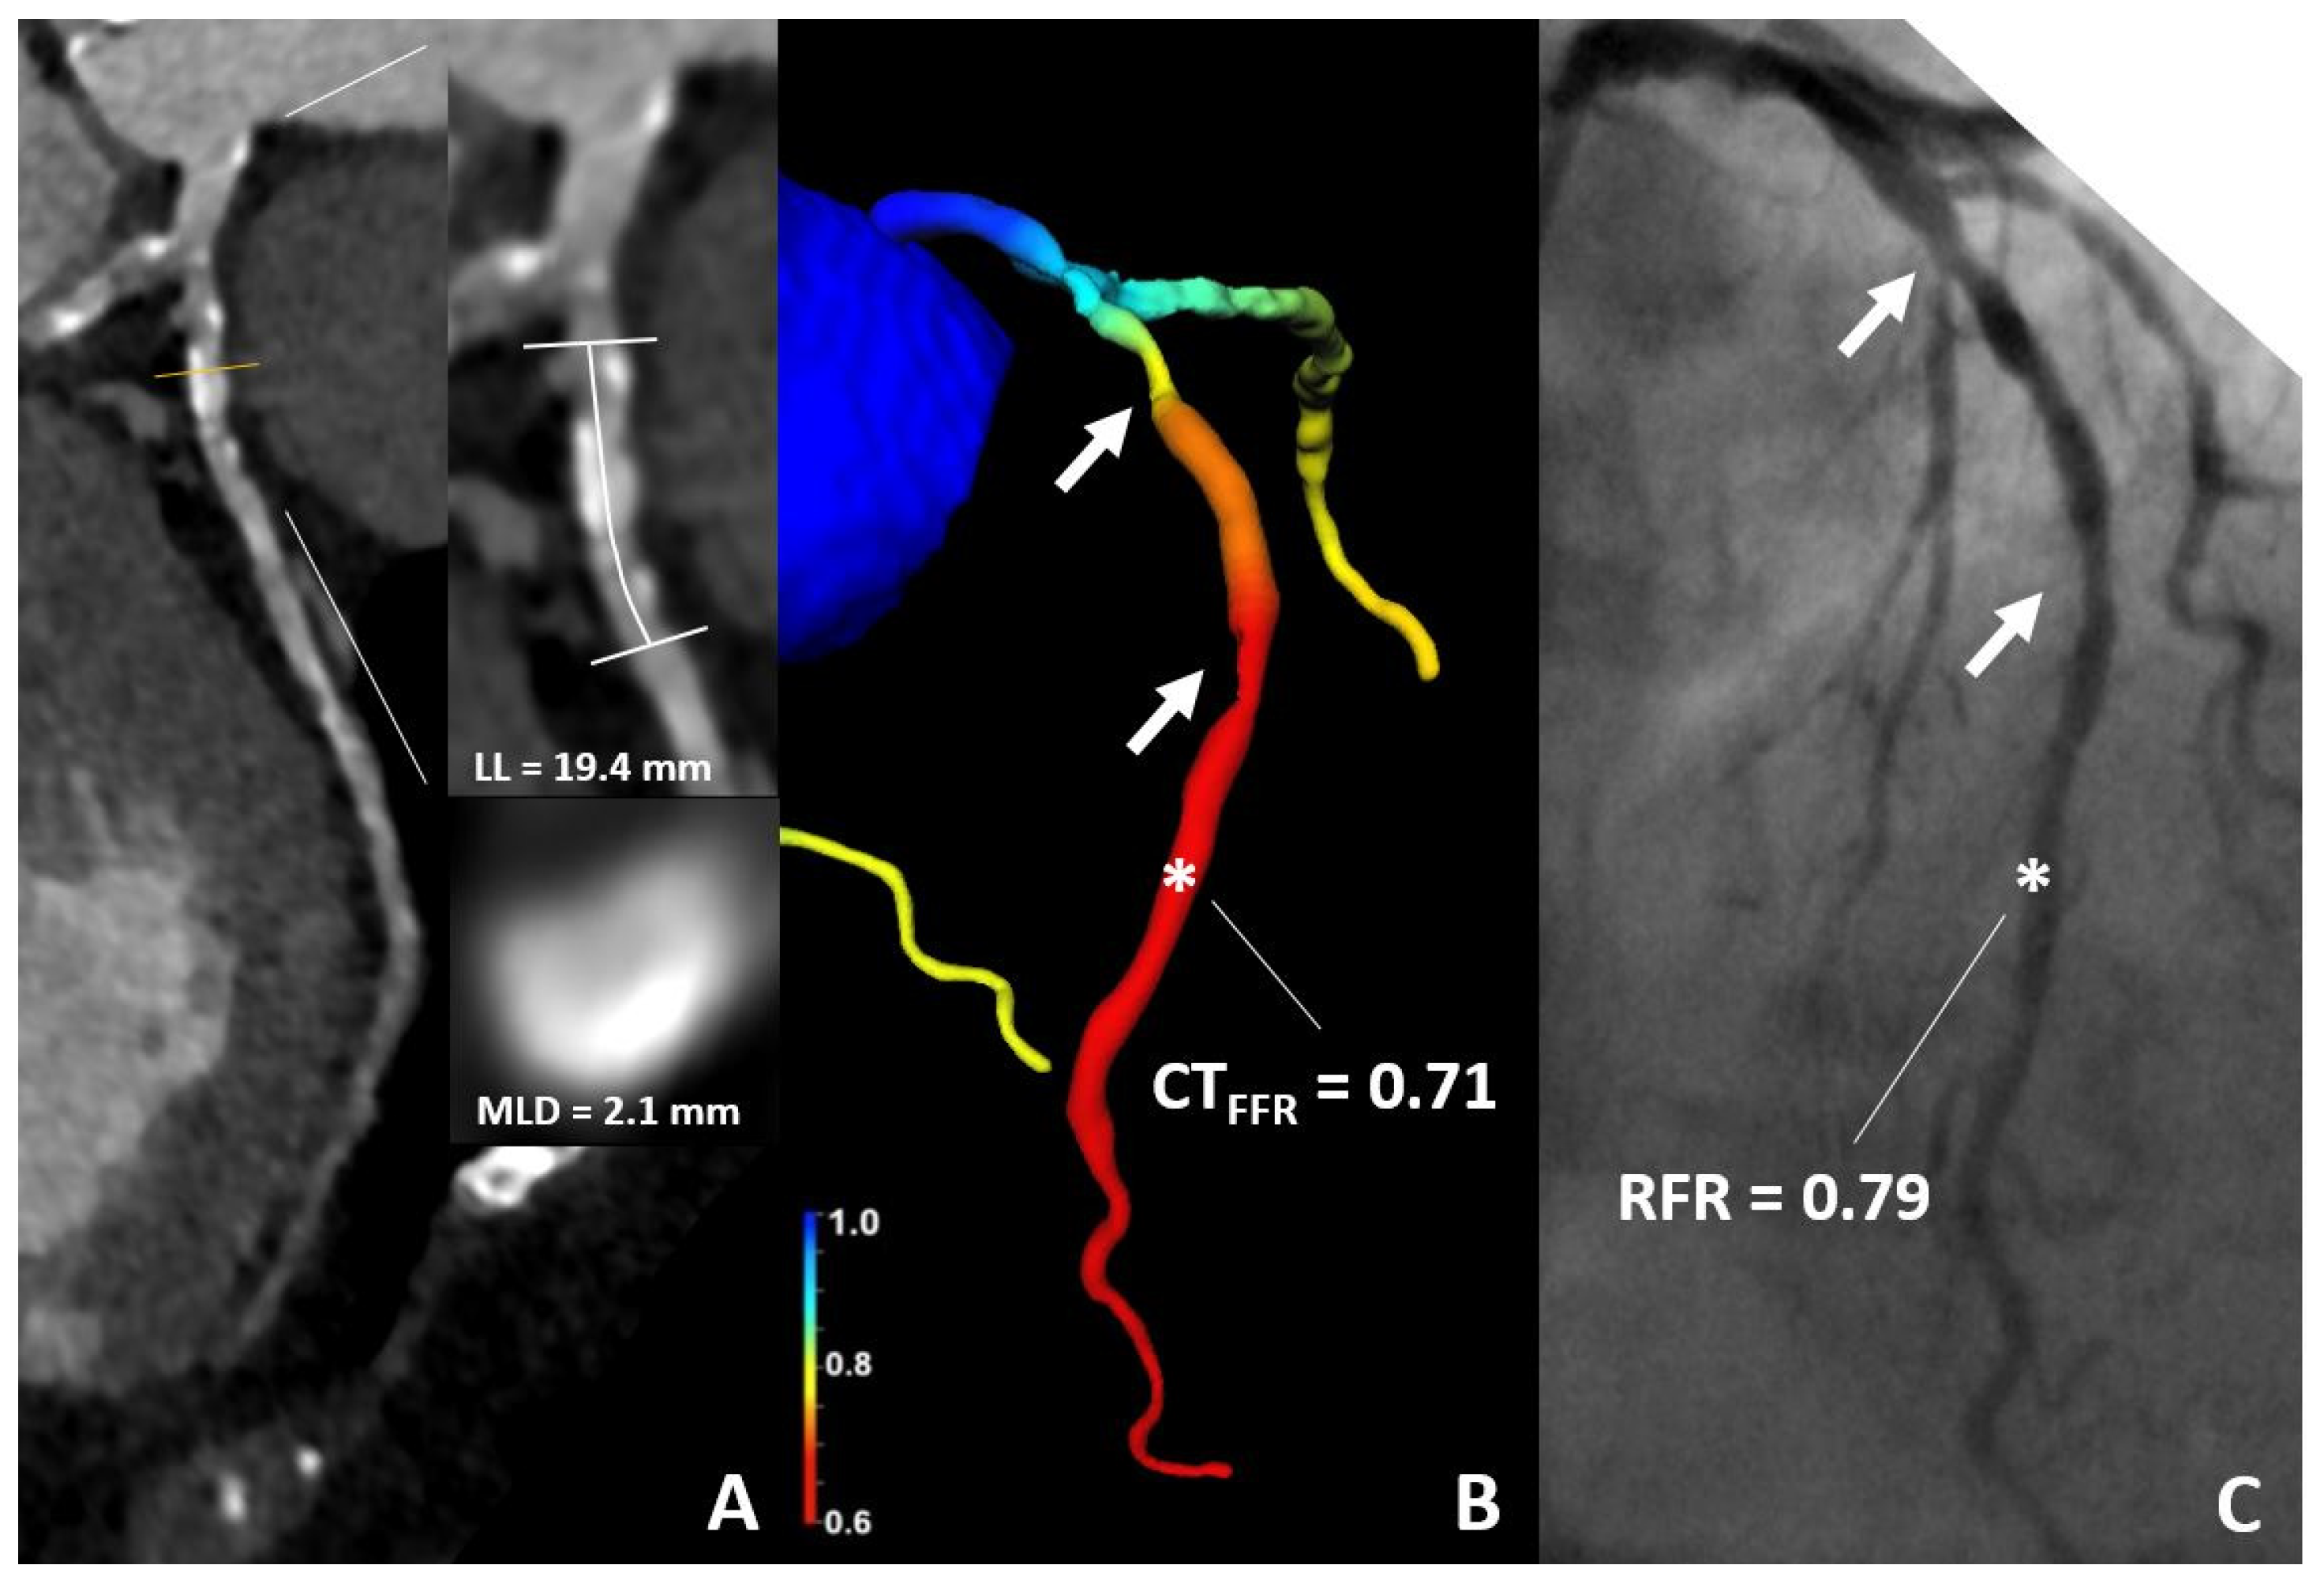

2.2. Acquisition and Analysis CT Datasets (CT-TAVR Image Reconstruction)

2.3. CT-FFR Analysis

2.4. Invasive Coronary Angiogram and Resting Full Cycle Ratio Measurement